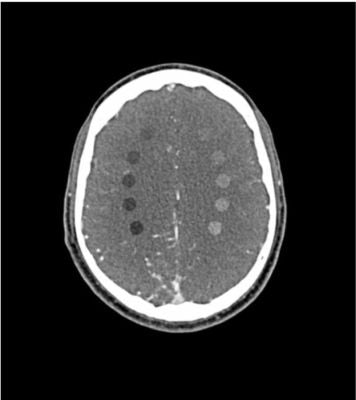

This phantom simulates a contrast medium-enhanced head in the arterial phase (CT angiography). It covers the vertex to the foramen magnum.

The phantom has 10 low-contrast lesions in the centrum semiovale and the right hemisphere has an arteriovenous malformation.

• 5 rod-shaped lesions on each side in the centrum semiovale at the periventricular and supraventricular level.